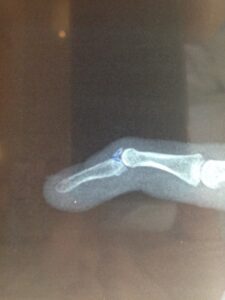

Απαραίτητος είναι και ο ακτινολογικός έλεγχος για την ύπαρξη αποσπαστικού οστικού τεμαχίου της φάλαγγος.

Χειρουργική θεραπεία συνιστάται σε αποτυχία της συντηρητικής θεραπείας. Πιο συγκεκριμένα, συνίσταται σε περιπτώσεις μη αποδοχής του ασθενή της εφαρμογής του νάρθηκα, όταν έχουμε διατομή του τένοντα σε ανοικτό τραύμα από τέμνων όργανο, ή όταν με την σφυροδακτυλία συνυπάρχει και οστική συμμετοχή (αποσπαστικό κάταγμα) που καταλαμβάνει περισσότερο από το το 1/3 της αρθρικής επιφάνειας.

Όταν συνυπάρχει σφυροδακτυλία με κάταγμα τότε εφαρμόζεται κλειστή ανάταξη του κατάγματος και σταθεροποίηση της φάλαγγος με μία ενδομυελική καρφίδα ή λοξή δια της άρθρωσης της τελικής φάλαγγος.